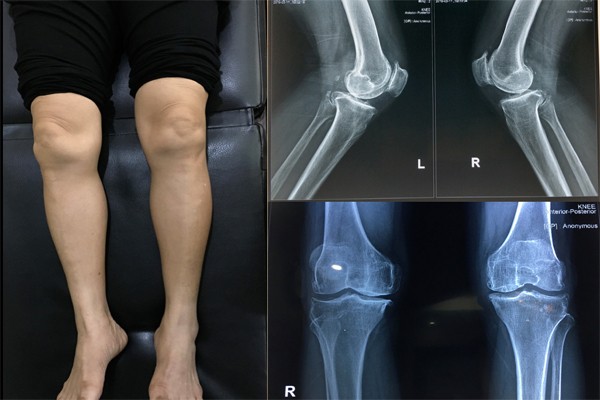

Đau nhức khớp gối ở người già là tình trạng phổ biến

Đau, sưng, cứng khớp là các triệu chứng đau nhức khớp gối điển hình

Các triệu chứng đau đầu gối chân dễ nhận biết nhất

Đau đầu gối gồm hàng loạt các triệu chứng điển hình sau:

Đau: Thường đau âm ỉ, có thể đau dữ dội sau khi vận động mạnh, đau giảm khi được nghỉ ngơi.

Sưng và nóng khớp: Đầu gối sưng tấy, đỏ, chạm tay vào thấy da ấm nóng.

Cứng khớp, khó co duỗi: Buổi sáng ngủ dậy thường bị cứng khớp, khó co duỗi. Thời gian bị co cứng thường kéo dài khoảng 30 phút.

Có tiếng lạo xạo, lục cục trong đầu gối: Khi khớp bị tổn thương, phần sụn khớp bị bào mòn mất độ nhẵn mịn, khớp xương không còn chất đệm nên khi di chuyển thường phát ra tiếng.

Chân tê bì: Dây thần kinh bị chèn ép nên lực chân yếu, gây cảm giác tê bì, giảm khả năng vận động.

Biến dạng khớp: Đầu gối sưng viêm có thể gây biến dạng lệch một bên hoặc lõm vào gây đau đớn.